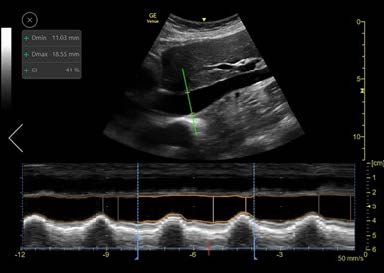

The Auto IVC tool is based on artificial intelligence. We collected thousands of IVC ultrasound images and trained our algorithm to perform the actions required for placing the AMM cursor line through the IVC in precise position (2-3 cm below the diaphragm). The algorithm then measures the maximum and minimum diameters of the IVC throughout a respiratory cycle (Fig.2).

Once the longitudinal view is acquired and the Auto IVC tool is activated, the system automatically locates the IVC and places an AMM cursor through it. The cursor tracks the longitudinal location within the IVC and the AMM automatically adjusts its tilt to maintain perpendicular incidence to the IVC. The user may tap on the image while scanning to choose a different location for the AMM as desired. The Auto IVC tool measures the maximum and minimum diameters of the IVC throughout the respirator cycles in real-time. The AMM timeline traces the diameter of the IVC over time and the collapsibility or distensibility index results are displayed in the measurements result window. Linear graphics on the AMM timeline indicate the minimum and maximum diameters and the user can readjust their positions, if desired, based on clinical judgement.

Figure 2: Auto IVC Tool Screen layout